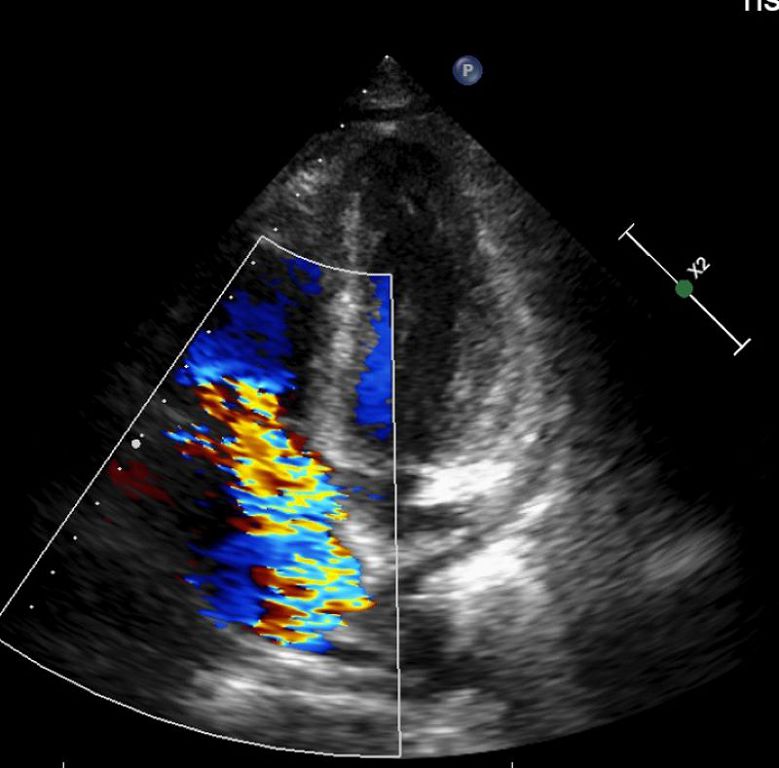

63歲的林先生去年底開始出現不明原因的反覆高燒,多次奔波診所與各大科別求診,卻始終找不到原因,因而來到台北慈濟醫院感染科就醫。抽血檢查顯示白血球、血小板及血紅素低下,必須輸血,但血液及骨髓等相關檢查均找不到病因,僅電腦斷層意外發現脾臟腫大與腹水。最後在住院的心臟超音波檢查中發現林先生罹患三尖瓣重度閉鎖不全,瓣膜上還長了一公分大的贅生物(即細菌感染的病灶),確診為感染性心內膜炎。會診心臟血管外科後,楊凱文醫師替其更換人工生物瓣膜,術中同步清除感染病灶。手術出院後,門診經過一段時間的追蹤,病人的血球數值明顯回升,感染也治療完全,順利恢復健康。

三尖瓣逆流並不少見,國外統計指出,有高達70%-80%的健康人群可見輕微三尖瓣逆流;但中重度以上的三尖瓣逆流發生率則較低,約占整體人口的1%-2%。大多數患者初期多無明顯症狀,直至中重度以上才會有輕微水腫出現,因此許多人往往會忽略其嚴重性,待出現嚴重問題時多已經變成重度逆流。楊凱文醫師表示:「三尖瓣逆流大多可以用藥物控制,若是進展為重度逆流且藥物治療效果不彰,同時合併右心室功能異常,就會需要手術,但臨床案例不多。」診斷上,會以超音波檢查為主,手術則會視病人狀況選擇開胸或微創手術。以林先生為例,考量病人血球數值極低、免疫力差,擔心術中出血,醫療團隊以開胸手術替其更換人工瓣膜,並同步清除感染的贅生物。